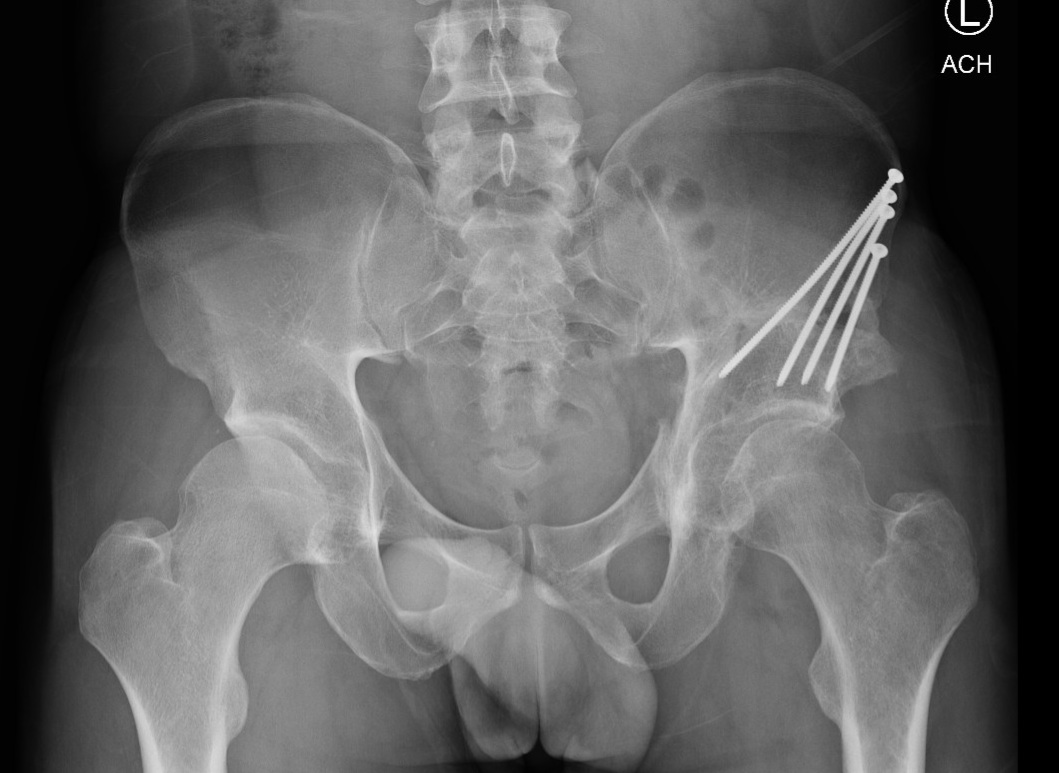

Periacetabular Osteotomy

Periacetabular osteotomy (PAO) is a joint-preserving surgery that repositions the hip socket to better cover the femoral head, treating hip dysplasia and improving joint stability. It helps reduce pain and delay or prevent arthritis in younger patients.